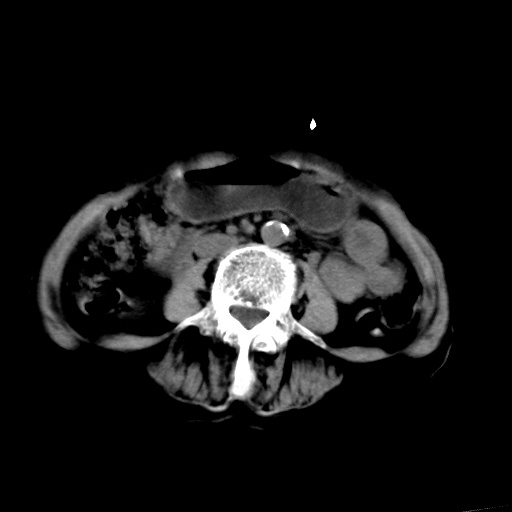

以下是引用杀毒软件在2009-3-4 17:38:00的发言:[br]为何没有喝照影剂呀? 胆总管及肝内胆管扩张,增强吧。[br][br]考虑-----十二指肠占位----建议----十二指肠镜检查[br][br]

以下是引用jiangjing在2009-3-4 17:45:00的发言:[br]低位胆道梗阻。十二指肠降段局部管壁增厚。扫描效果不理想,建议ct增强及ercp。

以下是引用杀毒软件在2009-3-4 17:38:00的发言:[br]为何没有喝照影剂呀? 胆总管及肝内胆管扩张,。增强吧。[br][br]考虑-----十二指肠占位----建议----十二指肠镜检查[br][br][br][br][本贴已被 杀毒软件 于 2009-3-4 17:56:38 修改过]